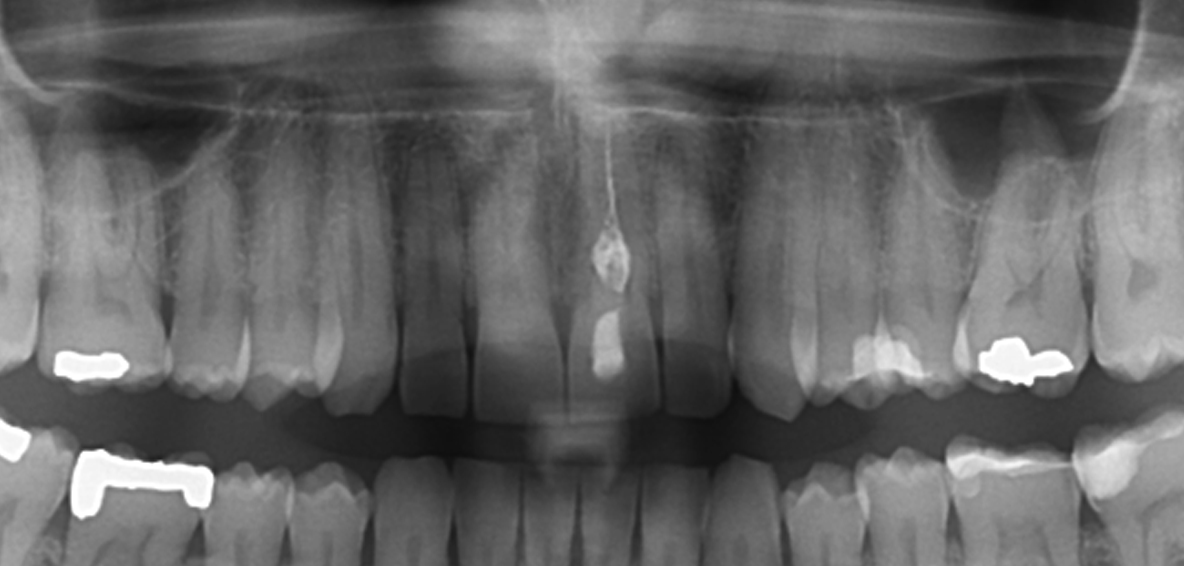

Salve, ho un incisivo scuro dovuto ad un devitalizzazione di circa tre anni fa a causa di un trauma di quand'ero piccolo! A seconda della luce si nota molto di più la differenza di colore! Ho già provato lo sbiancamento esterno senza risultato per quello interno invece mi è stato sconsigliato per via del pericolo di un riassorbimento canalare(come evidenziato dalla radiofrafia) Vorrei mettere la faccetta ma sono preso da mille dubbi pur avendo sentito molti dottori... Il mio dentista dice che non ci sono problemi ma il dente con la faccetta aumenterà leggermente di spessore inoltre mi sconsiglia di portarlo alla lunghezza dell'altro per paura che mi si possa staccare la faccetta! Un altro dentista mi ha detto che non ci sono problemi per quanto riguarda spessore e lunghezza (il dente sarebbe stato identico all'altro ) ma quando ha visto la radiografia mi ha detto che non se la sentiva di operare perchè il dente avrebbe potuto spezzarsi!!! Un terzo dentista mi ha detto che poteva venire un buon lavoro con il dente che avrebbe ripreso il suo colore naturale ma avrebbe limato molto per coprire il colore nella parte superiore! Pareri discordanti.... Non vorrei ritrovarmi se faccio la faccetta (corone e quant'altro le ho scartate perchè non vorrei ridurre troppo il dente) con un "dentone"! E se poi si vedrà la linea scura del dente tra faccetta e gengiva? Ho visto un sacco di foto su internet eppure nella maggiorparte (non in tutte beninteso) si vedeva l'artificio del materiale! La faccetta sarà liscia e innaturale o potrà replicare la "ruvidità" del mio dente! Sono mesi che ci penso e nel frattanto ho difficoltà a sorridere!

Caro Signor Carlo, buongiorno. Precisando che in simili Diagnosi sono necessarie Rx Endorali le sole precise ed utili per valutare l'Unità Dentale (Corona, Radice, Parodonto ed osso di sostegno e i rapporti coi denti prossimali ed antagonisti) e non certo le OPT che ha postato e non capisco perché le siano state fatte queste anzichè le endorali, facendole, tra l'altro, assorbire più Radiazioni, non necessarie, "Sic", sarei curioso di sapere se tutti questi Dentisti le abbiano fatto pagare la Visita! Sa consultarne tre e pagare la Visita, costa, forse più di una faccetta estetica.Presumo quindi che siano state tutte Visite Gratis e molto Brevi! La Visita Gratis propende a far pensare che il Dentista sia "mediocre". Non esiste qualità a costi bassi! Come in un centro low cost, a basso costo dove fanno la visita gratis, la panoramica gratis etcetcetc! Ma purtroppo come accade anche da molti Dentisti Privati che non capiscono che La visita Odontoiatrica, ripeto , è un atto medico essenziale e "carico della cultura del medico e non può non essere fatta "pagare" con un giusto Onorario! Quindi se vuole un consiglio, scelga solo chi inizi una terapia o proponga o pianifichi una terapia, qualsiasi essa sia, solo dopo una adeguata visita Odontoiatrica completa e "colta"! Una visita Odontoiatrica è un atto medico importante e colto che richiede almeno un'oretta oltre un'altra mezzoretta per informare il paziente (consenso informato). Mi scuso coi Colleghi di Dentisti Italia se mi sono ripetuto per l'ennesima volta ma questo comportamento "che purtroppo è figlio di questi nostri tempi malsani e di questa nostra Società decadente" deve cessare! Io faccio il possibile. Una Visita Odontoiatrica è la massima espressione Culturale e di conoscenza Medico-Odontoiatrica e, se fatta come si deve , impegna il Cervello del Dentista per un'ora circa più una mezzora per le informazioni doverose di "consenso informato"! Legga come faccio io una Visita leggendo sul mio Profilo "VISITA PARODONTALE", ma vale come visita Odontoiatrica generale, perché la visita che si fa nel mio studio, a prescindere dal motivo per cui è venuto il paziente, è questa e stia certo che tutte le patologie "saltano fuori"! Non è Lei che deve "capire" è il Dentista! E non troverà certo il Dentista da chi fa le Visite Gratis!Vada dal Dentista, scelto per Fiducia e Stima e non in base a visite gratis e preventivi apparentemente convenienti! Segua la "Vox Populi" o cerchi su questo portale in "Trova Dentista " in Home page digitando la città e leggendo i curricula. Poi digiti il nome del Dentista su un motore di ricerca e se il Professionista è uno studioso, troverà curriculum, foto di interventi, corsi, congressi, pubblicazioni. Non sarebbe indispensabile avere tutto questo, ma almeno sa che sta recandosi da un Dentista colto e che fa cultura, il ché è già un buon inizio! In bocca al Lupo. Si deve solo affidare a chi le dia una "sensazione" di Professionalità e quindi di Fiducia e di Stima. Non deve cercare Lei, di capire quale sia la Terapia più idonea. Se avesse queste pretese, si Laurei in Odontoiatria, prima! Curare la patologia che ha Lei è "normalissima routine". Lei sta Annegando in un bicchiere d'acqua e i Dentisti che ha consultato, non dimostrando "Polso ed Auterevolezza" stanno annegando con Lei"! Autorevolezza l'ha chi ha competenza che si traduce in decisione certa e sicura derivante dalla propria Cultura e Capacità Diagnostica! Si Diagnostica perché la Grande Assente, come al solito, è proprio la Diagnosi che è la conseguenza di una Visita Odontoiatrica Accurata e che impegna Dentista e Paziente per tanto tempo! Non basta un'occhiata e via! Non Bisogna valutare solo il Dente in questione ma analizzare tutto l'apparato Stomatognatico, Gnatologicamente, Parodontalmente, Conservativamente, Funzionalmente, Esteticamente. Tutto questo, senza estrapolare la "bocca" dal contesto dell'Organismo intero in cui si trova che va valutato quindi insieme alla "bocca", Clinicamente, Anamnesticamente, Semeiologicamente per fare Diagnosi Differenziali che Nascono Solo dalla conoscenza delle varie patologie ed emettere infine un sospetto Diagnostico che diventa poi Diagnosi Certa con, "Ragionamento Clinico e Strumentale e eventualmente analitico ematologico". Si emette così una Prognosi ed infine la Terapia ed ho detto "La", non "Una" Terapia che sceglie il Dentista e solo il Dentista! Cari saluti

Gentile sig. Carlo, ricordo che la preparazione per la faccetta non è distruttiva del dente, ma comporta il minimo per ricostruire il dente della stessa forma e dimensione. Quello che più mi sembra degno di attenzione è il fatto che il lavoro interno è poco apprezzabile, il riassorbimento interno importante, e vale la pena chiedersi il motivo di questa reazione del dente. Utile riguardare i contatti con gli inferiori, a volte un trauma da contatto nel tempo provoca un riassorbimento. Non credo che il dente nell'insieme sia così debole da non sopportare la preparazione di una faccetta, e anche il fatto che potrebbe alla fine aversi un dente sovracontornato è eccessivo. La realtà e che nessuno vuole metterci le mani, e questo dice che si rivolge alle persone sbagliate o che il dente è in sé un problema. Le consiglio un bravo dentista abile nella conservativa, e una faccetta allo zirconio e di-silicato di litio, assolutamente naturale. Un'altra cosa importante è che la radiografia non permette di vedere bene la chiusura dell'apice. Dovrebbe fare una piccola radiografia digitale per evidenziare la chiusura. Infine, in questi casi è opportuna una metodica di riempimento Shilder, crown down, perché c'è una dilatazione centrale. Un mondo di auguri

Premesso che dalla rx si vedono diverse carie sparse nei denti dietro, a mio avviso la unica vera soluzione è una capsula di ceramica integrale o anche di zirconia. La faccetta non può riuscire a coprire il colore bene. La capsula avrà anche lo scopo di proteggere il dente (non di rovinarlo) da fratture successive con la masticazione, perchè assai indebolito. Le capsule in situazioni come la sua proteggono il dente, non lo rovinano. E ripristinano una estetica totalmente perfetta se fatte da un bravo dentista che si serva da un valido tecnico artigiano italiano.

La cura canalare del suo incisivo non sembra congrua, serve una radiografia endorale per valutarla ed eventualmente impostare un ritrattamento endodontico (prima di protesizzare). Per quanto riguarda la parte protesica, se il dente è molto discromico deve essere limato molto anche in caso di faccetta estetica (le lumineers, fusci adesivi no prep, non sono adatte a denti particolarmente discromici in quanto non coprirebbero adeguatamente i colori scuri), faccetta estetica che può realizzare in composito o in disilicato di litio; se però, limando molto il dente per realizzare una faccetta (con probabile estensione palatale), il dente risulterebbe molto compromesso, allora sarà opportuno incapsularlo (corona in zirconia). Questo si stabilisce dopo aver eseguito una visita completa ed accurata, impronte e modelli di studio (su cui si realizzano le preparazioni pre - operatorie); una volta definito il piano di trattamento più adeguato al suo caso, si spiega al paziente e si procede. In entrambi i casi il risultato estetico è eccellente (nessun dentone, nessun bordino etc etc) ed il dente, anche se ridotto dimensionalmente, è protetto dalla struttura protesica.

Gent.mo Sig. Carlo, capisco che per lei sia difficile trovare un filo comune nel pensiero di tanti professionisti e quindi sono a dirle di non soffermarsi tanto sulle scelte proposte da uno o dall'altro. Ogni collega propone il meglio che sa di poter fare per ottenere un risultato che la possa soddisfare; non esiste in astratto un trattamento migliore di un altro ma il trattamento che soddisfi le sue personali esigenze e che il clinico sa di poter eseguire al meglio. Se un collega le propone una corona non lo fa per dispetto ma solo perchè nelle sue mani quello è il modo per ottenere il miglior risultato possibile. Allo stesso modo un collega che le propone una faccetta. Tuttavia, prima di disquisire sul risultato finale porrei molta attenzione alla cosidetta "parte invisibile" del lavoro, ossia alla devitalizzazione. Oggettivamente non vedo una bella situazione nella radice e ho dubbi e timori sull'esito finale della cura canalare. Dico ciò perchè sarebbe molto spiacevole trovarsi con una bellissima corona o faccetta di cui lei è soddisfattissimo ma che verrebbe vanificata da un processo di riassorbimento radicolare che causerebbe la perdita del suo dente. Le consiglio, quindi, di farsi eseguire una devitalizzazione a regola d'arte ed una ricostruzione in composito e perno in fibra di quarzo; ciò permetterà di seguire nel tempo l'evoluzione del suo dente che, se positiva, potrebbe essere finalizzata con una corona oppure con una faccetta. Nella speranza di non averle confuso troppo le idee le porgo cordiali saluti.

il Dr. Carpinteri mi ha rubato le parole di bocca... facendo un corretto ritrattamento endodontico sarà possibile, senza pericoli, effettuare lo sbiancamento interno. I risultati sono spesso buoni/ottimi. Non sempre così stabili (un po' di recidiva ci può essere). Solo a qual punto si può valutare una faccetta personalizzata eseguita in laboratorio (non una industriale) e cercare di "copiare" il dente adiacente.